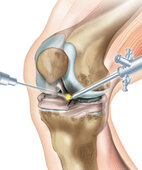

Schlüsselloch-Operation am Knie: Ärzte reparieren gerissene Bänder meist im Rahmen einer Gelenkspiegelung (Arthroskopie)

Die Operation am Knie erfolgt üblicherweise minimalinvasiv, in "Schlüssellochtechnik" über eine Gelenkspiegelung (Arthroskopie). Das bedeutet, der Arzt setzt sehr kleine Schnitte, durch welche dünne optische Instrumente (eine Kamera zur Bildgebung) und Operationsinstrumente in das Gelenk eingeführt werden (siehe Grafik oben). Der Eingriff kann stationär oder ambulant erfolgen.

Im Rahmen einer solchen Gelenkspiegelung (Arthroskopie) können die Ärzte das Gelenk genau inspizieren. Gleichzeitig kann hierüber die Therapie erfolgen. Zum Beispiel kann bei einer vorderen Kreuzbandruptur das Band durch ein neues aus körpereigenem oder sehr selten aus körperfremdem Material rekonstruiert werden. Dafür werden Teile gesunder Sehnen aus der Beinmuskulatur des Patienten oder aus der Kniescheibensehne (Patellasehne) in einem offenen Eingriff entnommen und als Ersatz für das gerissene Band eingesetzt und verankert.

Ebenso können eventuelle Verletzungen an Knochen, Gelenkkapsel oder Menisken gesehen und therapiert weren.

Eventuell gehen Ärzte auch in Etappen vor: Zunächst untersuchen sie zum Beispiel das verletzte Gelenk per Gelenkspiegelung, entfernen dabei gleich die Bandstümpfe des gerissenen Bandes, nähen den abgerissenen Meniskus wieder an oder entfernen ihn teilweise. Der Patient erhält anschließend über einige Wochen Physiotherapie, bis das Gelenk ganz abgeschwollen ist. Dann erfolgt – per erneuter Arthroskopie – die eigentliche Reparatur des Bandes. Die Operation sollte nur stattfinden, wenn das Gelenk nicht überwärmt oder gerötet und wieder normal beweglich ist.